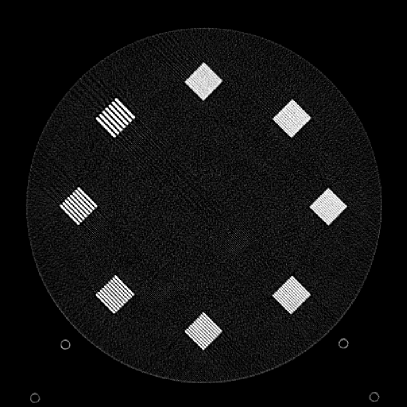

To evaluate image quality, we first tested the performance of JENG on a standard CT phantom, CT ACR 464 phantom 35. Then we tested JENG on 5 clinical thoracic datasets and 3 abdominal datasets. The ACR 464 phantom contains four modules in total, with each module 40 mm in depth and 200 mm in diameter. The first module has 4 different inserts to test CT number fidelity. In addition, the module contains a series of wires for cross-plane resolution evaluation, shown as white horizontal bars near the center in Fig. 9(a), and are visible in 0.5 mm z-axis increments. The second module tests low contrast resolution, but is not used in this paper. The third module, shown in Fig. 9(b), is a uniform cylinder of water-equivalent material of 0 Hounsfield units (HU), and we used this module to quantitatively measure image noise profile and in-plane resolution. The fourth module consists of resolution bars of various spatial frequencies for analysis on high contrast resolution. To scan the phantom, the scanner setup used dual sources with 2 focal spots at each source. In addition, the projections were acquired using the same protocol for clinical thoracic scans with 100 KV, a nominal tube current of 718 mA and a high helical pitch of 2.8. For all experiments, we compared JENG against the state-of-the-art Siemens ADMIRE, reconstructed with a BL-64 soft tissue sharp kernel, and we define ADMIRE as the clinical standard hybrid IR method for the rest of the paper.

Figure 10: Clinical Standard hybrid IR vs JENG performance, with a display window center of 650 HU and a window width of 1500 HU. The spatial frequencies for bar patterns from top going clock-wise are 1.2, 1.0, 0.9, 0.8, 0.7, 0.6, 0.5, 0.4 mm-1. (a) The clinical Standard hybrid IR at L1 denoising strength using a soft tissue high contrast kernel. Note that significant aliasing streaking artifacts are present near the bar patterns. (b) JENG at a comparable L1 noise level but with much clearer bar pattern and fewer artifacts than the clinical standard hybrid IR. (c) The clinical standard hybrid IR at a stronger denoising strength of L3. (d) JENG at a comparable L3 noise level.

The first experiment we performed was a visual comparison of in-plane spatial resolution between JENG and the clinical standard hybrid IR. We used the ACR phantom module 4 for this evaluation, which has 8 resolution bars of various spatial frequencies from 0.4 mm-1 to 1.2 mm-1. To obtain a fair comparison, we matched the image noise variance in the uniform regions of JENG and the clinical standard hybrid IR and studied their in-plane spatial resolution and undersampling streaking artifacts. In addition, we performed two sets of experiments. The first set of experiments matched their image noise variance at the L1 denoising strength of the clinical standard method with a noise variance of 33926 in the uniform regions. The second set of experiments matched their image noise variance at stronger L3 denoising strength of the clinical standard method with a noise variance of 12988 in the uniform regions.

Fig. 10 is an example image for resolution bars and the spatial frequencies for the bar patterns from top going clockwise are 1.2, 1.0, 0.9, 0.8, 0.7, 0.6, 0.5 and 0.4 mm-1. Fig. 10(a) is the resolution bars reconstructed by the clinical standard hybrid IR at L1 denoising strength. Fig. 10(b) is JENG reconstructed at an image noise variance comparable to the L1 denoising. Fig. 10(c) is the clinical standard hybrid IR at a stronger L3 denoising strength and we can observe that the result at L3 denoising leads to less image noise than the result at L1 denoising in Fig. 10(a). Fig. 10(d) is JENG at an image noise variance comparable to the L3 denoising. To help readers better see the image quality difference between the clinical standard hybrid IR and JENG, Fig. 11 is the difference image between the two algorithms at L1 denoising. A noticeable difference between the clinical standard hybrid IR and JENG is that the clinical standard method in Figs. 10(a) and (c) have strong undersampling aliasing artifacts near the phantom periphery, which show a pattern of high density streakings and the streakings point along the direction of X-rays. In addition, the magnified sub-figures show that the bar pattern at 0.8 cycles/mm is unresolved with blurry details. In contrast, JENG in Figs. 10(b) and (d) effectively decimates the undersampling artifacts and the bar pattern in the magnified sub-figures of JENG is completely resolved with clearer details.

For the clinical standard hybrid IR, a possible cause for its loss of image resolution and the presence of aliasing artifacts in the image periphery can be explained by the Nyquist-Shannon sampling theorem. Nyquist-Shannon sampling theorem concludes that the discrete projection sampling rate for an application that requires Fourier Transform and data interpolation must be sufficiently high to avoid alias in the frequency domain and capture all the needed information in the continuous image domain. Given that the clinical standard hybrid IR involves Fourier Transform and data interpolation operations, the low projection sampling rate at a high helical pitch of 2.8 might lead to aliasing artifacts and a loss of spatial resolution for the clinical standard method. In contrast, JENG has no Fourier Transform or data interpolation operations and is completely based on linear algebra and acquisition physics modeling. Therefore, JENG is not limited by Shannon-Nyquist Theorem and its images are less susceptible to aliasing artifacts and show clearer bar patterns.